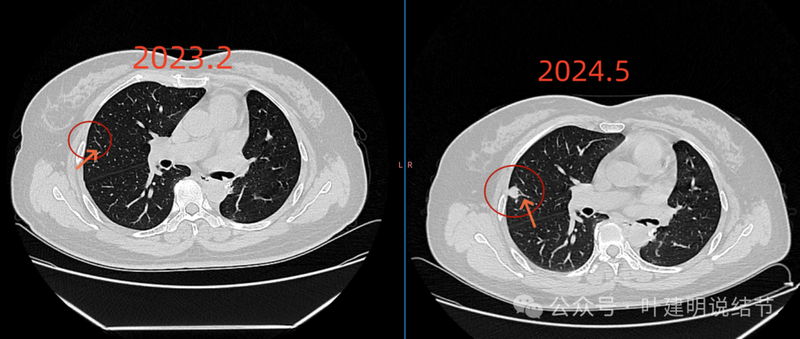

2023年2月时右上叶同一处没有明显病灶。

右上前后相差15个月的对比。

我的想法是这样:第一、我看了你术前的片子,左下病灶是混合磨玻璃密度,但实性成分并不是明显聚着的,而只是整体密度略显高而已,有毛刺、有血管进入,靠近叶间裂与胸膜。这种密度的病灶转移的概率应该不高的。而且这次右上的病灶是实性的,形态与原来的左下病灶明显不一致的。所以首先我觉得不像转移。第二、右上病灶在一年前的2023年2月一点都没有,在比较短的时间内突然出现并快速进展的话,要么是炎性的,要么是恶性程度比较高的,比如低分化癌或小细胞癌这些。单纯从影像上分析,右上这个病灶感觉多中心,有支气管截断征,有血管进入,胸膜了有轻微牵拉,整体轮廓较为清楚,周围肺野比较清晰,感觉与恶性更为符合;第三、从是否马上干预来讲,如果积极点,穿刺下或直接单孔胸腔镜下切除并术中送快速切片以确诊,并依术中快速病理再决定是否切肺叶,这也是可以的。但真恶性,我前面说了恶性程度估计不低,要有血行微转移估计也已经转移了,适当随访下再对比再决定手术与否亦是可行的;而若实际上非恶性,则适当随访或抗炎后复查更不会延误治疗。当然若查下PET-CT也是可以的。总体我的意见是:倾向恶性点,但建议适当观察随访下并对比后再决定手术与否。意见供参考!